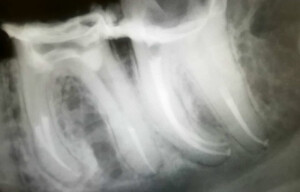

La radiographie 2D numérique de contrôle

À la fin de l’opération d’endodontie, une radiographie de contrôle est effectuée. Celle-ci a pour but de confirmer le succès du protocole ; elle vérifie que le traitement a obturé l’intégralité de la longueur des racines de la dent dévitalisée. Les appareils de radiologie modernes sont désormais sur le mode numérique et considérablement moins ionisants que les modèles argentiques anciens.